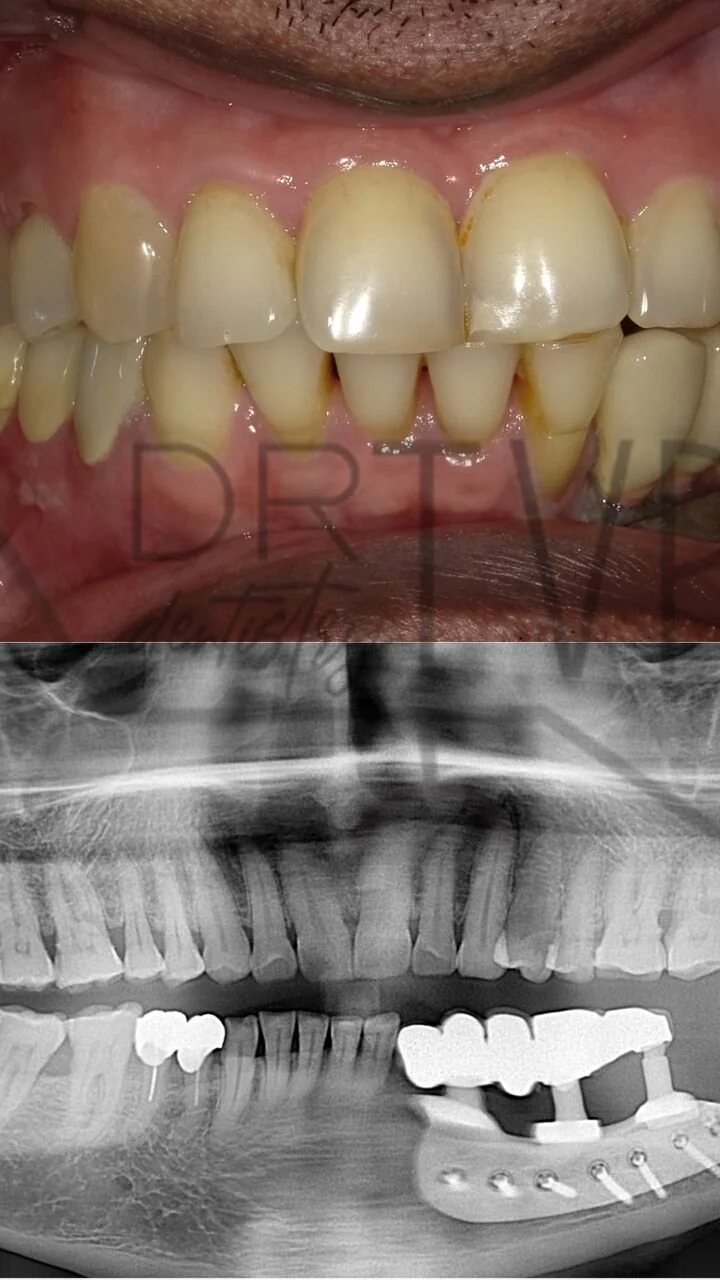

Restorative dentistry focuses on repairing or replacing damaged or missing teeth. These procedures help improve oral health and function. Common dental restorations include crowns, bridges and implants

Implants are biocompatible titanium screw like replacements of roots, which serve to support and replace teeth that have been lost due to decay, periodontal disease, trauma etc.,

These implants are placed within the jaw bone via an atraumatic, painless procedure. Once they heal and fuse with the bone, they may be used to replace the missing tooth/ teeth.